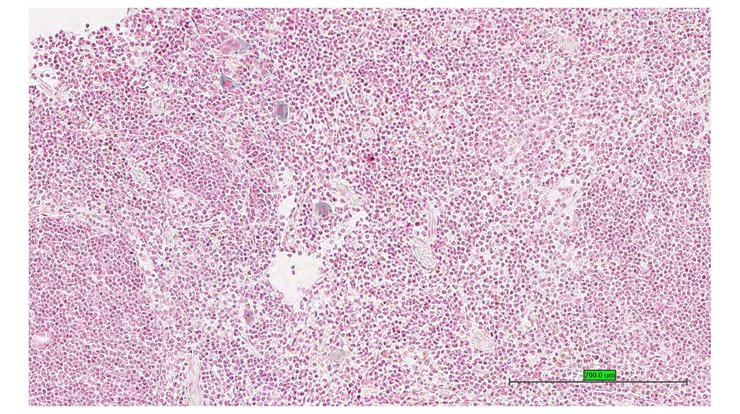

Specimen UC Davis_1885947: postnatal adult; Ubxn2atm1b(EUCOMM)Hmgu/Ubxn2a+ (more )

Structure Level Pattern Image Note

TS28: spleen Present UC Davis_1885947

Specimen UC Davis_1885948: postnatal adult; Ubxn2atm1b(EUCOMM)Hmgu/Ubxn2a+ (more )

TS28: spleen Present UC Davis_1885948